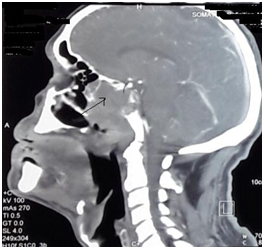

A sixty-four year old patient with a recently diagnosed medical history of unregulated high blood pressure, consulted for severe ptosis of the left eye associated with pain along the ophthalmic nerve’s territory which was progressing rapidly within 20 days. The ophthalmological examination revealed a best-corrected visual acuity of 7/10 for the right eye and 3/10 for the left. Manual rising of the left upper eyelid unveiled a divergent eyeball associated with a subtotal restriction of eye movement (Figure 1). Further examination with the slit lamp showed a nonreactive mydriasis. The cerebral MRI indicated a malicious tumor of the left posterolateral cavum wall invading the left cavernous sinus and the hypopharynx (Figure 2). A biopsy was conducted and confirmed a poorly differentiated epidermoid carcinoma. The patient’s assessment of extent was negative, therefore, benefiting of several radio-chemotherapy sessions. Follow-ups had shown an improvement of visual acuity, decreased ptosis and increased ocular motility (Figure 3).

Figure 2CT scan image showing the cavum tumor